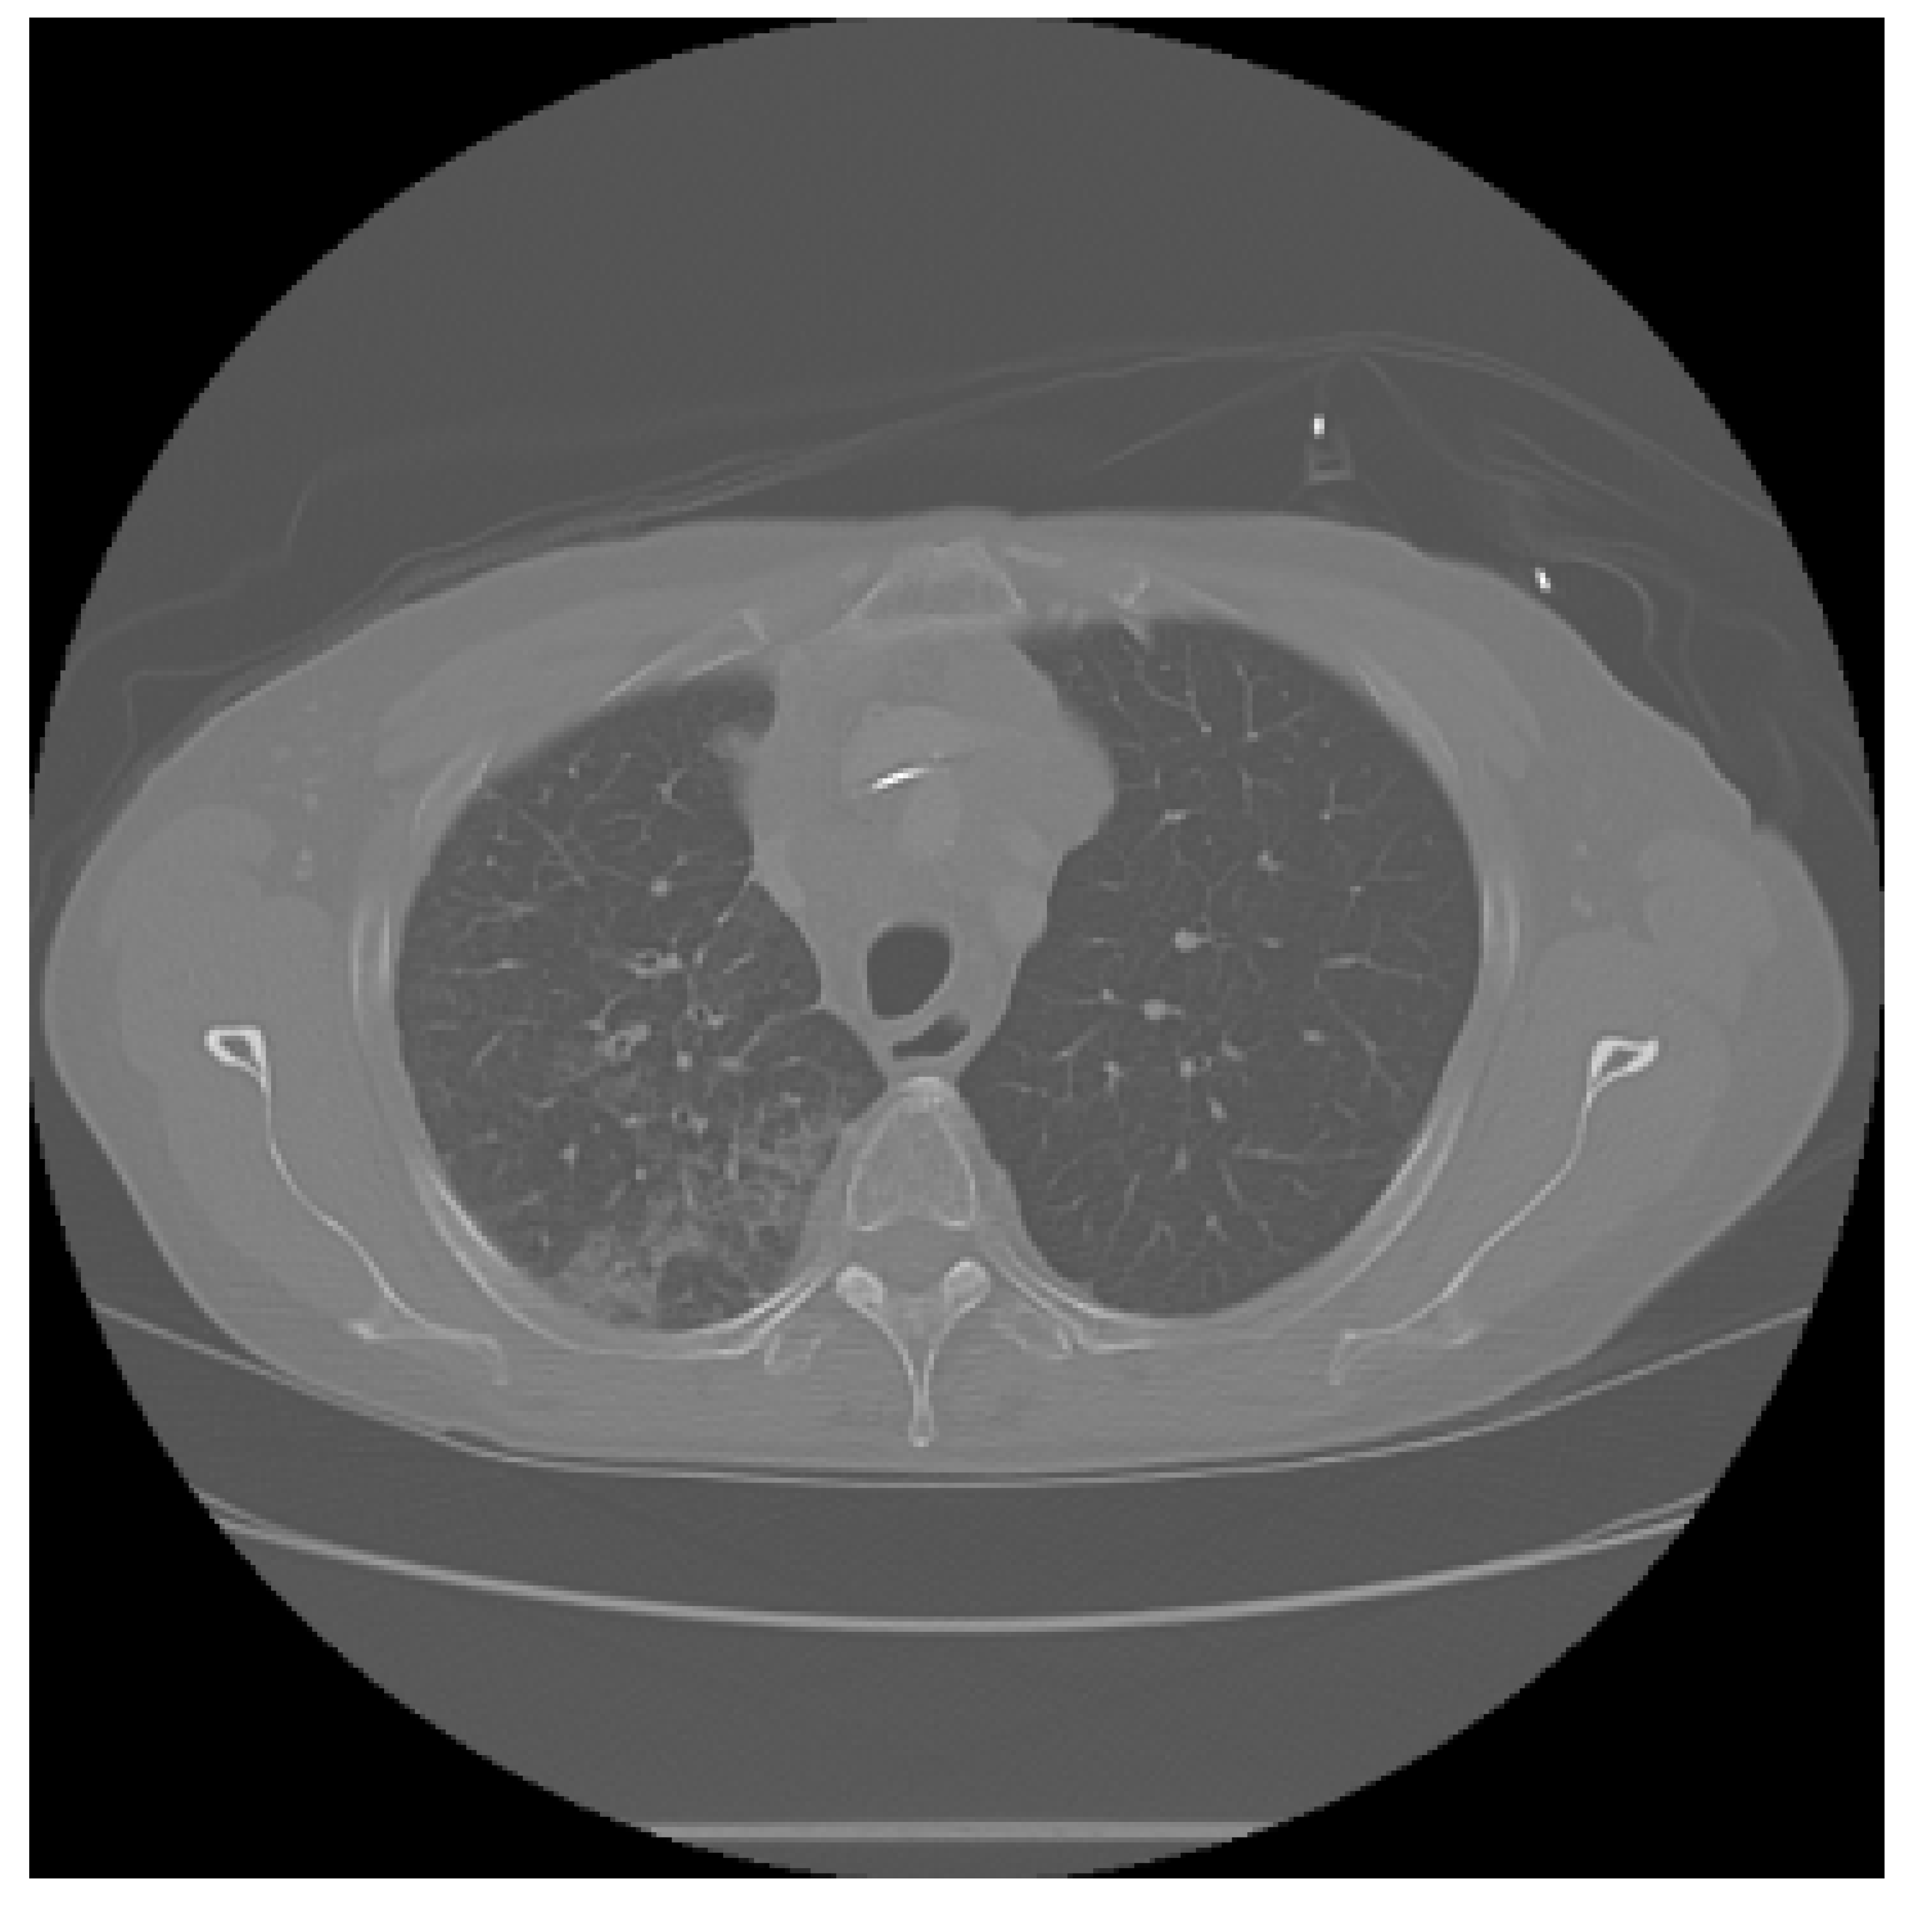

The APILungCancer interface provides intuitive functionality for loading and analyzing DICOM medical images. In the Load DICOM Images section, users can select and process CT scans for lung cancer evaluation. Once an image is loaded and analysis is performed, the software presents a visualization of the image along with the predicted probability of cancer (Table 7). Our study focused on lung cancer, including subtypes such as adenocarcinoma, squamous cell carcinoma, and small cell carcinoma. About 1000 training images and 300 test images from the CMB-LCA dataset were used to develop and validate the system.

In this example (Figure 5), the DICOM image 1-27.dcm from the test set was processed and the software calculated a cancer probability of 0.4267 (42.67%), indicating a high likelihood of malignancy.

Figure 5.

Determination of the probability of lung cancer. Example output of the system for the image 1-27.dcm, yielding a predicted probability of 42.67%, consistent with Table 7.

This value matches the result in Table 7, confirming the consistency of the predictions generated by the AI-based model integrated into the system.